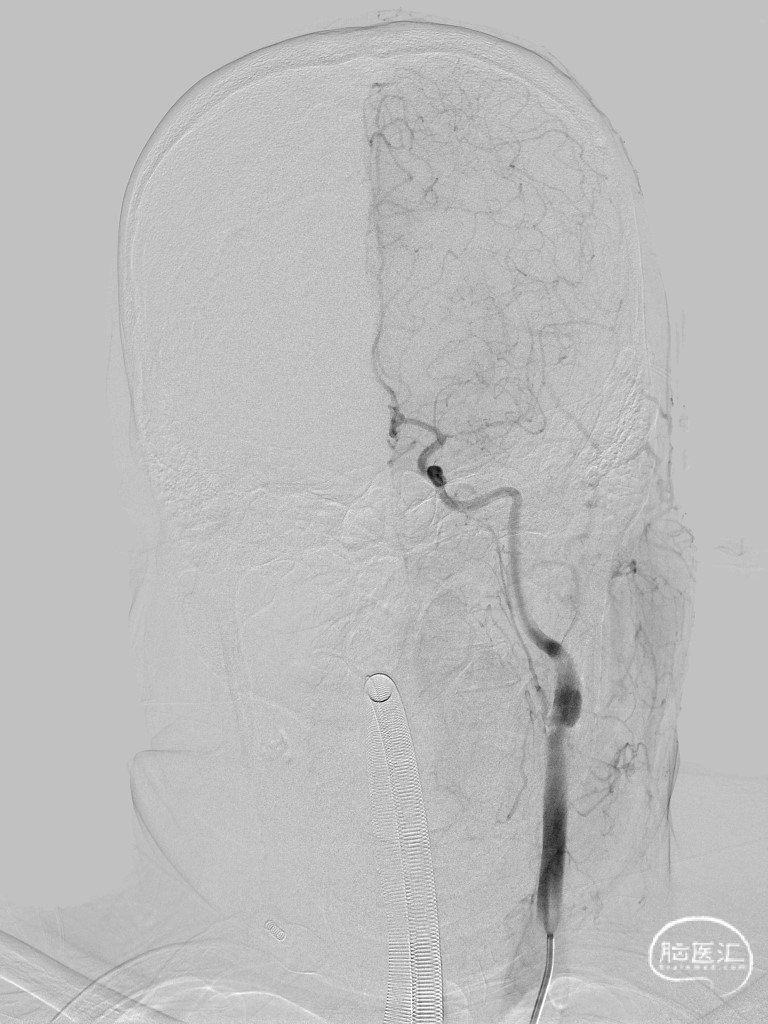

➢ 脑血管造影

经Stiff导丝更换6F金属长鞘,泥鳅导丝引导中间导管至左侧C2段;0.014inch微导丝导引微导管越过左侧大脑中动脉M1段闭塞病变段。

微导管造影提示位于血管真腔。

微导丝交换,分别以通桥白驹®颅内球囊扩张导管 1.25*8、1.5*10mm球囊扩张,复查造影血管狭窄程度较前好转。

经微导丝交换支架微导管,沿微导管送入4*39mm自膨支架至左侧大脑中动脉M1段闭塞病变处,支架成功打开,贴壁良好,支架内血流通畅。

➢ 术后造影